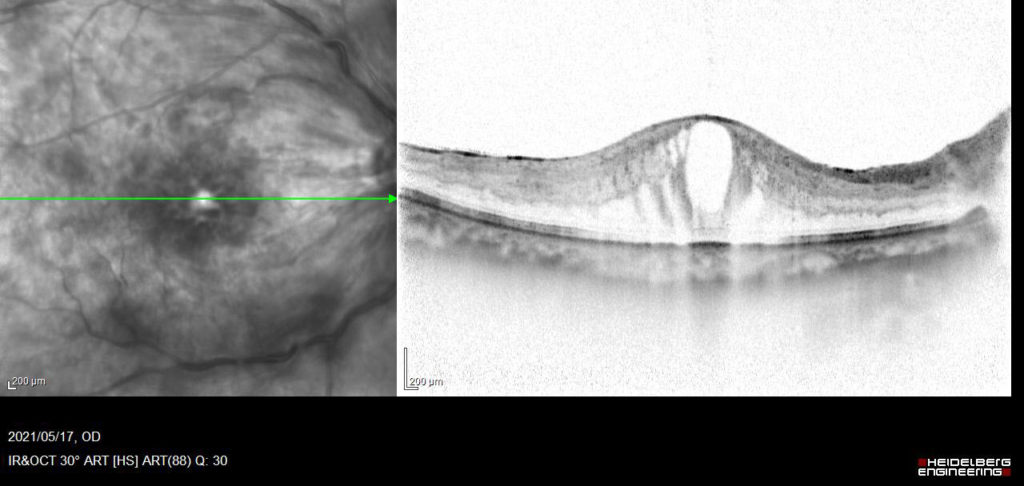

発症後約10か月、抗VGEFの硝子体注射後5Wで黄斑浮腫のみられない状態が維持できるようになった。

現在、経過中。rubeotic glaucoma 血管新生緑内障の発症なし。

視力 右眼 0.09(n.c)